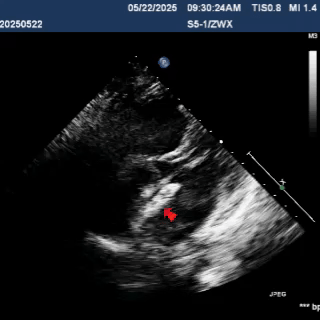

术中复测缺损大小

缺损大小为24.1mm

超声多切面观察封堵器位置形态,封堵器骑跨于缺损左右两侧

主动脉短轴切面显示封堵器呈Y字型抱住主动脉根部,夹持稳定

剑下两房心切面下观察,封堵器位置正确、形态良好

该病例术中复测房间隔缺损大小为24mm,断缘距下腔静脉14.2mm,距上腔静脉15.8mm,前后边缘各为10.1mm、16mm。房水平左向右分流。

封堵器左右盘面释放后,主动脉短轴切面显示封堵器呈Y字型抱住主动脉根部,通过牵拉实验,封堵器位置固定,未见明显位移及形变,多切面观察封堵器形态良好,无残余分流,封堵手术成功。